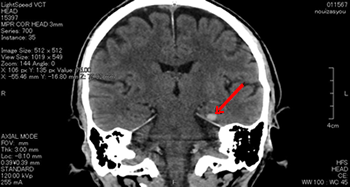

左顔面部を強打した脳挫傷の事例

CT画像では、中央部右側に白い○状の形があるのが読み取れます。これが脳挫傷が生じた部分です。

これは、バイクを運転していたところ、自動車と出合い頭で衝突した被害者のものです。左顔面部を強打し、左下顎骨骨折、左頬骨骨折となり、左下からの突き上げる衝撃で、左側頭葉に局在性の脳挫傷が発症したものです。